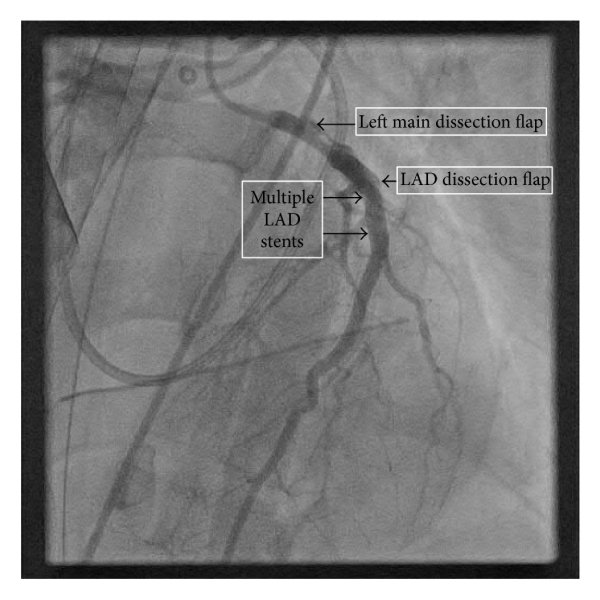

Right Coronary Artery (RCA): Dominance right. Large caliber, no significant stenosis. Angiographically normal with TIMI 3 flow. Left Main (LM): On first contrast injection afterJL engagement, mild ostial contrast staining was observed. On the second injection, there was more pronounced staining with dye hang-up, consistentwith catheter-induced LM dissection with suspectedpropagation toward the LAD/LCX.

- Actions: Stopped contrast injections; converted to RFA for stronger guide backup. Wired LAD and LCX in true lumen (confirmed by IVUS).

- Stenting: LM ¡æ LAD drug-eluting stent (DES) to seal LM entry; mini-TAP to LCX for ostial coverage.

- Imaging: IVUS pre-PCI confirmed dissection/intimal flap with intramural hematoma extending into proximal LAD/LCX; post-PCI showed good expansion/apposition, no residual entry.

- Final result: TIMI 3 flow in LAD and LCX; LM sealed; no residual flow-limiting dissection.